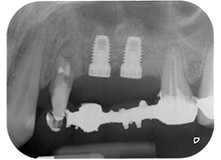

Schließlich wurde die Stelle nach einer Periostschlitzung mit resorbierbarem Nahtmaterial der Stärke 5/0 passiv mit einem koronalen Verschiebelappen vernäht (Abb. 15). Die postoperative Röntgenaufnahme zeigt beide Implantate in korrekter vertikaler Position (Abb. 16).

Die Abbildungen 17 und 18 zeigen das klinische Ergebnis zwei Monate nach dem Eingriff. Die nun verminderte Beweglichkeit des Zahns 24 lag bei Miller-Klasse 1 und das Weichgewebe war entzündungsfrei. Um eine neue Infektion zu verhindern und das epitheliale Attachment nicht zu zerstören, wurde auf eine Sondierung zu diesem Zeitpunkt verzichtet. Die nächste Untersuchung sollte bei der Freilegung und dem Verschrauben der Gingivaformer stattfinden, sechs Monate nach dem Einsetzen der Implantate.